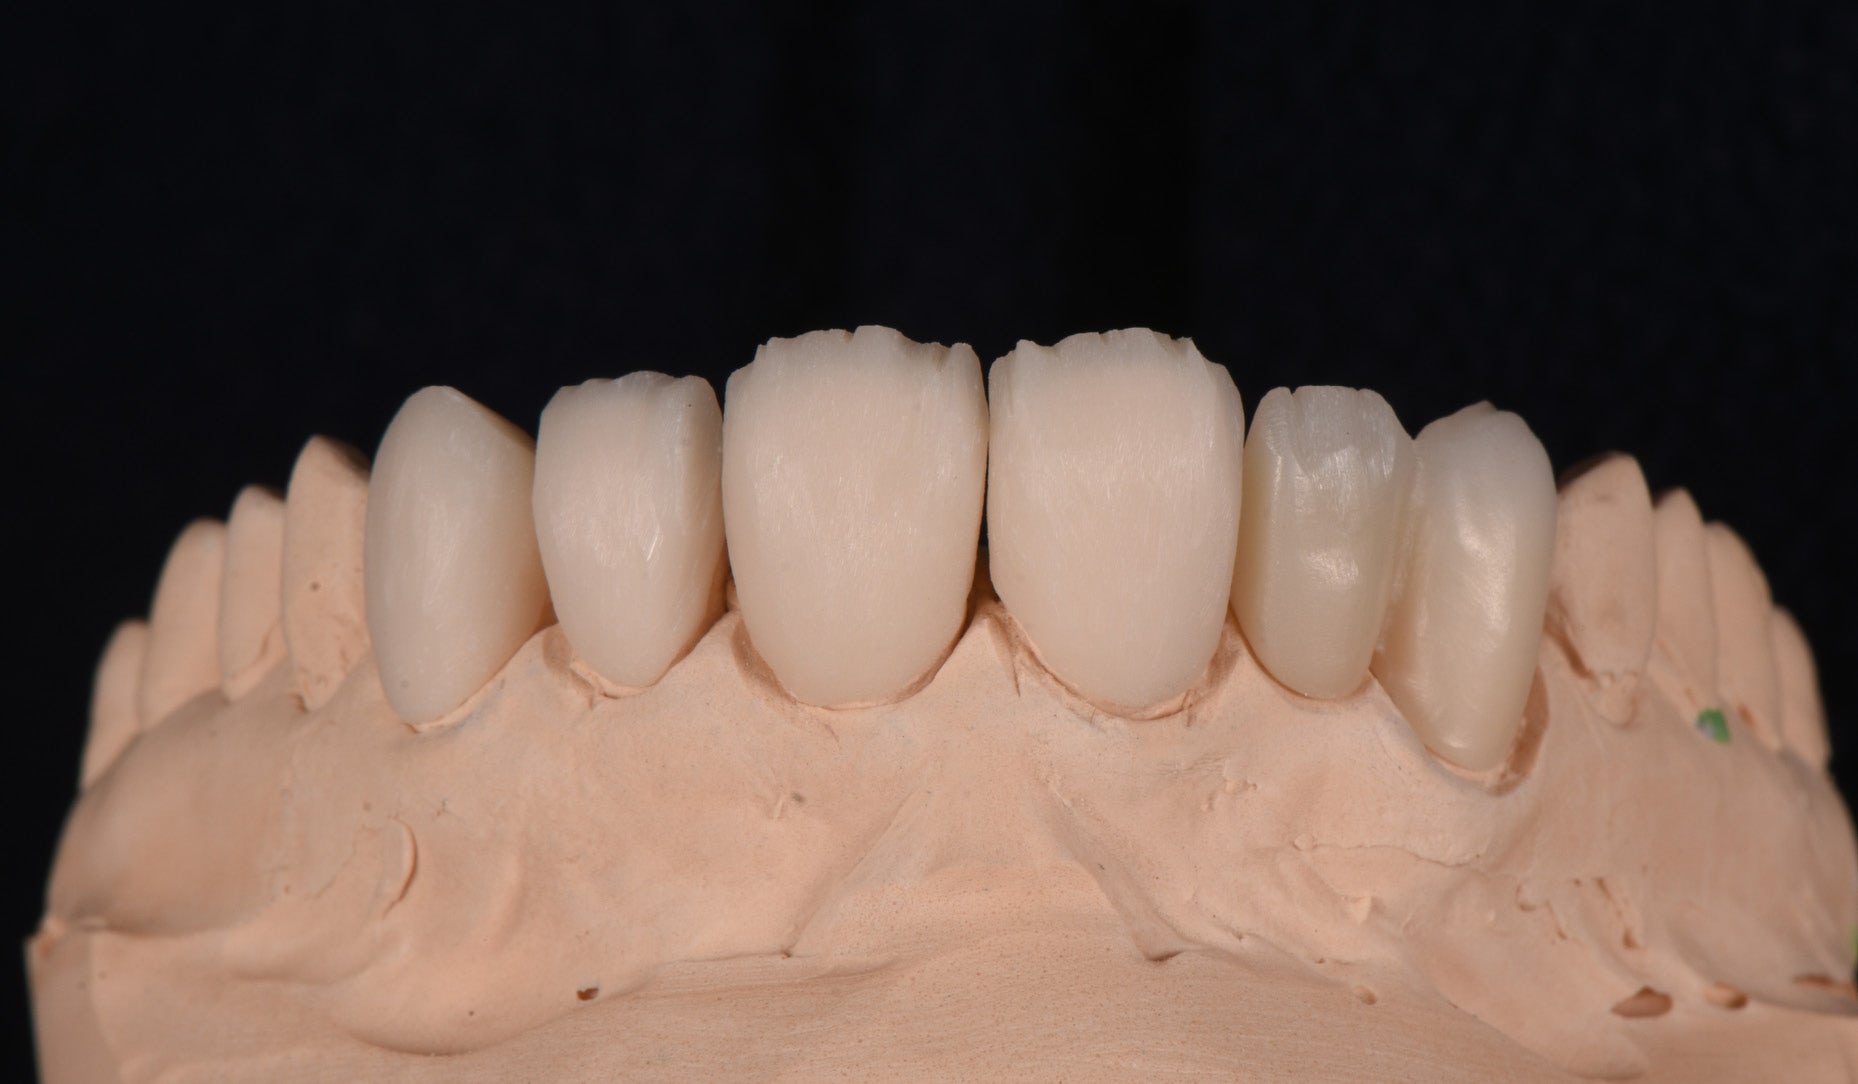

Clinical Cases, Labside Two high-strength ceramics, one micro-layering system Case by DT Andreas Chatzimpatzakis AESTHETIC AND EFFICIENT SMILE MAKEOVER Most patients asking for a smile makeover desire custom solutions rather than an off-the-peg smile: Individual tooth shapes that fit their face and their character, an internal play of colours that matches their age and natural dentition. Modern dental materials allow us to deliver what they demand in many situations – usually at a reasonable price. For a long time, however, we have been facing challenges when combining cosmetic and medically indicated treatment – e.g. a smile makeover including the rehabilitation of a missing lateral incisor. A straightforward solution – using lithium disilicate veneers alongside a zirconia cantilever bridge, both finished with their respective porcelain systems – would have been complicated by potential differences in the final appearance. With CERABIEN™ MiLai (Kuraray Noritake Dental Inc.), a set of internal stains and porcelains designed for micro-layering, the situation is different: Suitable for micro-layering on zirconia and lithium disilicate, it supports its user ideally in creating a harmonious smile even when the two framework materials are combined. A NEW CUSTOM SMILE The following patient case is a perfect example: A female patient with a missing lateral incisor, multiple visible composite restorations in the anterior region and an enamel fracture at her incisal edge desired a smile makeover. The selected materials were Amber Press LT (HASS), shade A1, for four veneers on the central incisors and the left lateral incisor and canine (teeth # 11, 21, 22 and 23 according to the FDI notation) and KATANA™ Zirconia YML (Kuraray Noritake Dental Inc.), shade A2, for the planned cantilever bridge on the maxillary right canine, replacing the missing lateral incisor (teeth # 12 and 13). Fig. 1. Female patient with a missing maxillary lateral incisor and multiple composite restorations in the anterior area – a smile makeover is desired. Fig. 2. Patient with mock-up. Fig. 3. Minimally invasive preparation through the mock-up, which takes into account the minimum space required for the planned materials and restorations. Fig. 4. Teeth prepared for the all-ceramic restorations. Fig. 5. Occlusal view of the maxillary teeth after tooth preparation. Fig. 6. Full-contour veneers and cantilever bridge on the model. Fig. 7. Restorations after a cutback limited to the vestibular and incisal area. Fig. 8. CERABIEN™ MiLai LT1 is applied to the middle and cervical area of the zirconia cantilever bridge. Fig. 9. CERABIEN™ MiLai Value Liner 2... Fig. 10. … and Value Liner 1 applied to the incisal area of the central and lateral incisor restorations. Fig. 11. CERABIEN™ MiLai porcelain Creamy Enamel mixed with Value Liner 2 (70/30) added to the middle and cervical areas of the four lithium disilicate restorations to increase and control the value. Fig. 12. ... while E2 is added to the incisal area of both canines. Fig. 13. Restorations covered by a layer of Tx ... Fig. 14. ... and LTx. Fig. 15. Appearance of the restorations after the first bake. Fig. 16. Adding translucency and opalescence to the cervical area with LT1 and brightness to the ridges with Creamy Enamel. Fig. 17. Completion of the enamel surface with a cover layer of LTx, which is responsible for a high translucency and opalescence. Fig. 18. Result of the second bake. Fig. 19. Final restorations with a natural self-glaze effect on the model. Fig. 20. Final restorations with a natural self-glaze effect in the patient’s mouth. Fig. 21. Smooth optical integration of the restorations. Fig. 22. Beautiful treatment outcome. CONCLUSION With the described approach and selected materials, it was possible to create restorations with a natural shade, shape and texture. They matched not only the appearance of the remaining natural teeth, but also showed internal consistency across the selected framework materials. The technical procedure was quite straightforward and efficient, while the result speaks for itself. Special thanks to Dr. Kanellos Ioannis for the collaboration on this case and for kindly providing the pre- and post-treatment photographs that complemented it. Dental technician: ANDREAS CHATZIMPATZAKIS Based in Athens, Greece, Andreas Chatzimpatzakis is the founder and director of ACH Dental Laboratory (since 2000), specializing in refractory veneers, lithium disilicate, zirconia, and implant prostheses. He graduated in Dental Technology from the University of West Attica and received advanced training in all-ceramic restorations in Helsinki and Japan under renowned masters including Shigeo Kataoka. Since 2017, he has served as an international trainer for Kuraray–Noritake Dental Inc., delivering lectures and hands-on courses worldwide on advanced ceramic techniques. He has also held roles as Key Opinion Leader for MPF Brush Co., Ambassador for Hass Co., and Editor-in-Chief of Laborama. An active member of the Hellenic Academy of Aesthetic Dentistry, his work and articles have been published in both Greek and international journals. Jan 21, 2026 Dental Technician Kuraray Noritake Prosthodontics Clinical Case Katana Zirconia YML CERABIEN MiLai Prosthetic dentistry Lab Dental Ceramics Cad Cam Discs KATANA Zirconia YML View Product CERABIEN MiLai View Product Subscribe to our Newsletter Join thousands of dental professionals and receive free advice that can help you and your career. We will not spam or share your e-mail.